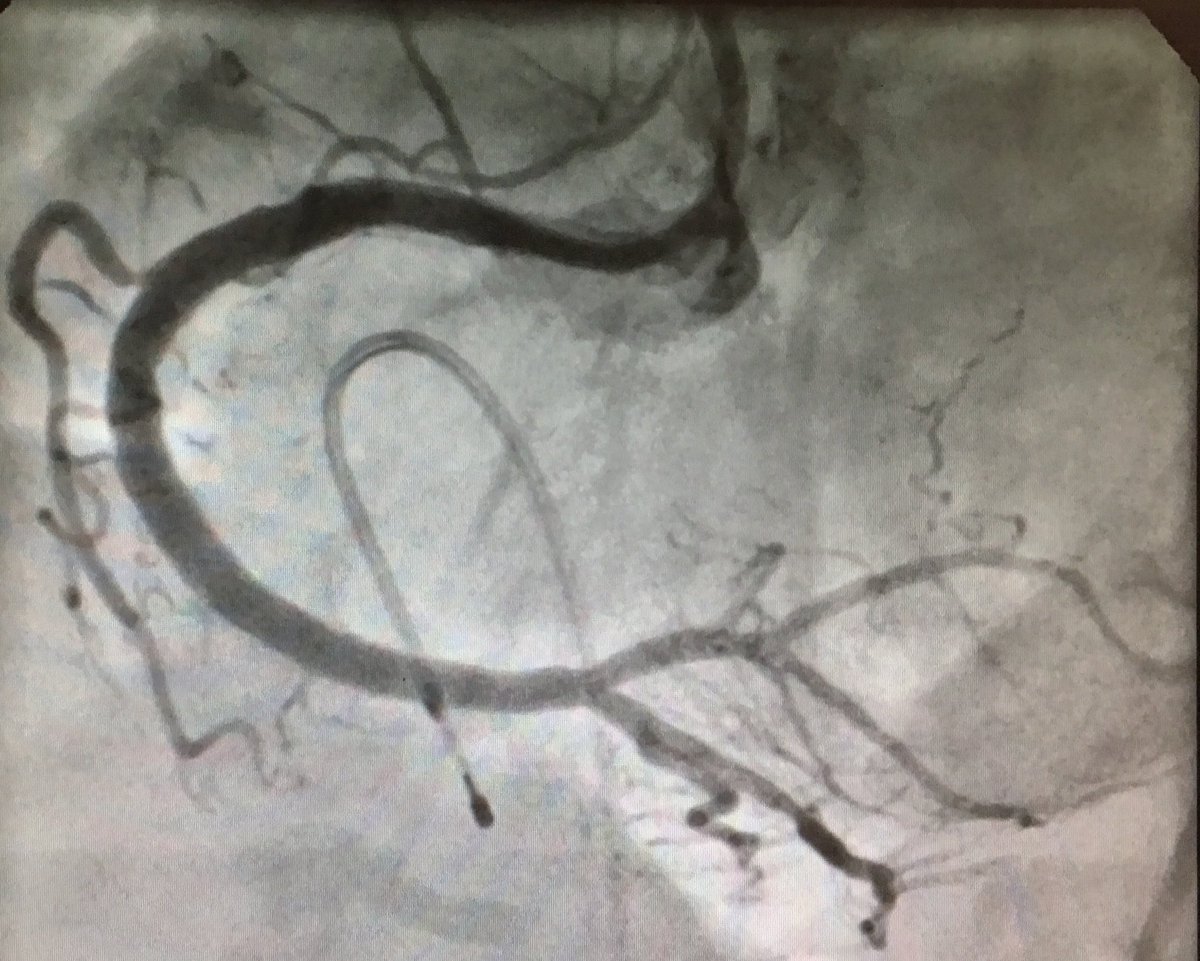

LCx Rotablation is always challanging. Successful LCx Rotablation in 50 Male, class III angina with previous failed attempted PCI. 1.25 Burr at high speed did the trick. excellent result. #CardioTwitter #rotablation #KGMU

DrAshishCardio's tweet image. LCx Rotablation is always challanging. Successful LCx Rotablation in 50 Male, class III angina with previous failed attempted PCI. 1.25 Burr at high speed did the trick. excellent result.

#CardioTwitter

#rotablation

#KGMU